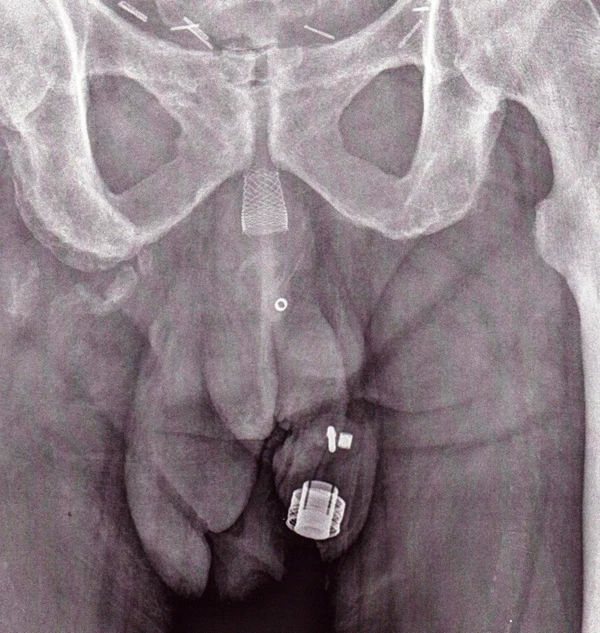

- Искусственный мочевой сфинктер с пружиной или 2-компонентное устройство: манжета и помпа.[3][4] Манжета располагается вокруг мочеиспускательного канала, а помпа имплантируется в мошонку. Давление в гидравлическом контуре создается пружиной помпы. Давление в ретропубикальном пространстве не оказывает никакого влияния на сфинктер данного типа.

Другой моделью ИСМП является ZSI 375 (Zephyr Surgical Implants, Женева, Швейцария), представлена в 2008 году.[11] Это цельное двухкомпонентное устройство с манжетой и помпой со встроенной пружиной. Оно поставляется как единое целое, предварительно соединенным и заполненным.[1][12] В ZSI 375 нет брюшного компонента, что наряду с его полной готовностью к имплантации сокращает операционное время.[13] Кроме того, отсутствие абдоминального разреза позволяет избежать постоперационного рубцевания а забрюшинном пространстве.[14][15] Еще одним преимуществом модели ZSI 375 является возможность увеличивать или уменьшать давление внутри устройства после имплантации для достижения желаемой степени сдерживания и удовлетворенности пациента. В частности, эти корректировки помогают контролировать сдерживание мочи в случае постимплантационной уретральной атрофии или задержки мочи (плохой отток мочи).[16][17][13] Регулировка давления может быть выполнена в амбулаторных условиях путем добавления или удаления дополнительного стерильного физиологического раствора при помощи шприца через мошонку.[12] К 2019 году во всем мире было имплантировано более 4,500 искусственных сфинктеров мочевого пузыря ZSI 375.[11]

| ZSI 375 | Zephyr Surgical Implants | Швейцария | 2008 | 2-компонентное устройство: манжета, помповый механизм | Да | Пружина из нержавеющей стали встроенный в помповом механизме имплантирующийся в мошонке | Да |